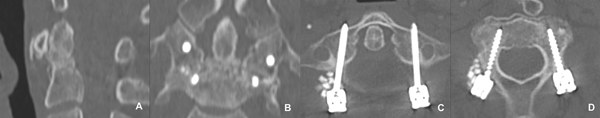

Los estudios de control alejados evidenciaron correcta artrodesis del segmento, lo cual se ilustra con los casos descriptos. (Figura 9 y 10).

Figura 9. Caso 1: TC Postoperatoria.

A. Corte sagital que evidencia la artrodesis del trazo fracturario. B. - D. Imagenes mostrando la posición de los tornillos: corte coronal (B.) donde además, se observa la artodesis anterior; corte axial a nivel de C1 (C.) y de C2 (D.).

Figura 10. Caso 2: TC Postoperatoria.

A. Corte sagital que evidencia la reducciónn del fragmento. B. - D. Imagenes mostrando la posición de los tornillos: corte parasagital (B.) donde además, se observa la artodesis anterior; corte axial a nivel de C1 (C.) y de C2 (D.).